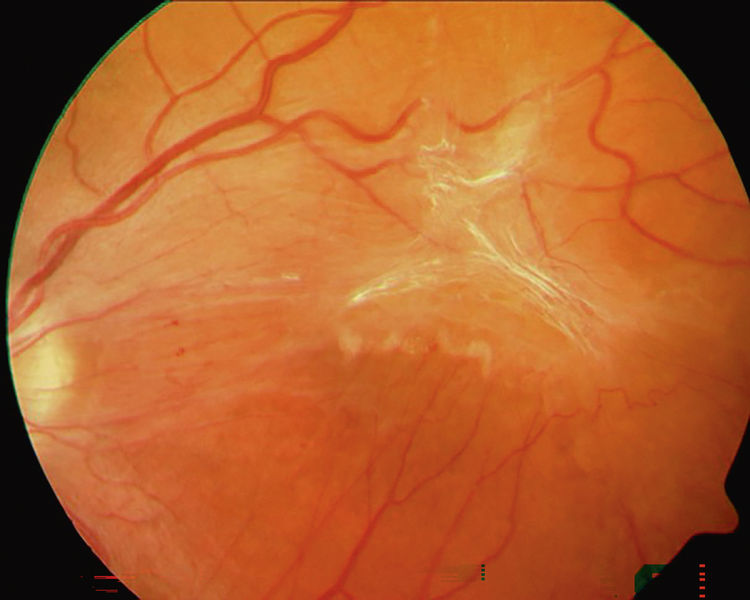

Ein 68-jähriger Patient stellt sich in der Sprechstunde vor. Er beschreibt eine Visusminderung am linken Auge. Vorausgegangen war eine unkomplizierte Operation des grauen Stars mit Implantation einer Hinterkammerlinse. Der Patient ist ein wenig enttäuscht, da der subjektiv empfundene Visusanstieg links nicht den Erwartungen und dem Ergebnis am rechten Auge entspricht. Besonders beim Lesen bemerkt er ein Verkippen der Buchstaben, es fällt ihm schwer, die Lesezeile zu halten. Ferner beklagt er ein verzerrtes Bild beim Sehen mit dem linken Auge (Metamorphopsie), welches beim Test mit dem sogenannten Amsler-Gitter (Abbildung 1) reproduzierbar ist. Hierbei blickt der Patient auf einen Fixierpunkt in der Mitte eines karierten Blattes und beobachtet den Verlauf der Linien um denselben. Im Rahmen der Visusprüfung wird die Sehschärfe des linken Auges für die Ferne mit 0.5 gemessen, rechts beträgt sie 1.0. Im Rahmen der direkten Funduskopie mit der 78dpt Lupe zeigt sich im Bereich der Makula ein glitzernder Oberflächenreflex, eine grauweissliche membranöse Struktur mit zugbedingten Netzhautfalten am hinteren Pol. In der durchgeführten OCT-Untersuchung erkennt man auf der Netzhautoberfläche eine hyperreflektive membranöse Struktur, die darunter liegenden Schichten der Netzhaut erscheinen in der horizontalen Ebene verworfen und sind erschwert voneinander abgrenzbar (Disorganization of Retinal Inner Layers: DRIL). Die Traktion überträgt sich bis in die äußeren Netzhautschichten, hier kommt es zu einer traktiven Elevation der Photorezeptoren im Bereich der Fovea („cotton ball sign“).

Abbildung 2: Ausgeprägter Befund einer epiretinalen Gliose, die als flächenhafte, weissliche Membran gut erkennbar ist. Ausgeprägte Verziehungen der retinalen Gefäße sind Hinweis auf die starken Traktionen durch die Membran und erklären die funktionellen Beschwerden des Patienten.